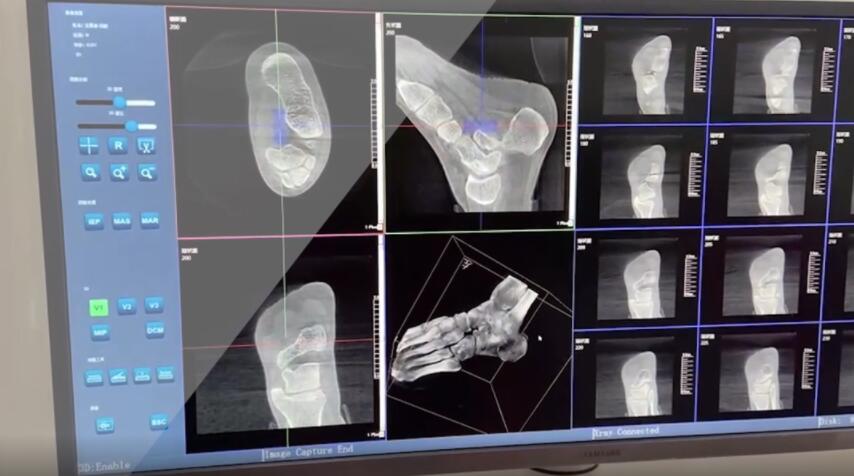

踝關(guān)節(jié)是人體中負(fù)重較大的關(guān)節(jié),也是活動(dòng)度較大的地方,所以對(duì)于足踝部位的關(guān)節(jié)內(nèi)骨折,我們更需要做到“解剖復(fù)位”。對(duì)于這種關(guān)節(jié)內(nèi)的骨折,尤其是踝關(guān)節(jié)內(nèi)部的骨折,不僅需要進(jìn)行X影像平片正側(cè)位的拍攝,由于在二維影像上無(wú)法判斷關(guān)節(jié)面的受損情況,往往還需要進(jìn)行三維影像的檢查。

在術(shù)前,我們需要做三維掃描的CT檢查,我們必須要有CT的片子,還要有三維的重建。

在術(shù)中,我們?cè)趺慈ヅ袛嚓P(guān)節(jié)面平不平整呢?常規(guī)的正側(cè)位影像是不能判斷的。有些醫(yī)生為了準(zhǔn)確的判斷,可能會(huì)選擇做開(kāi)放性的手術(shù),把關(guān)節(jié)暴露出來(lái),在眼睛的直視下判斷關(guān)節(jié)面平不平整。但是關(guān)節(jié)全部打開(kāi),無(wú)疑增加了病人的創(chuàng)傷,而且增加了患者的恢復(fù)時(shí)間。所以如果在術(shù)中我們有三維影像的支持,對(duì)醫(yī)生做手術(shù)而言就會(huì)事半功倍,而且能夠大大的增加手術(shù)準(zhǔn)確度,增加患者術(shù)后的預(yù)后。所以在術(shù)中有三維影像的支持是非常必要的!